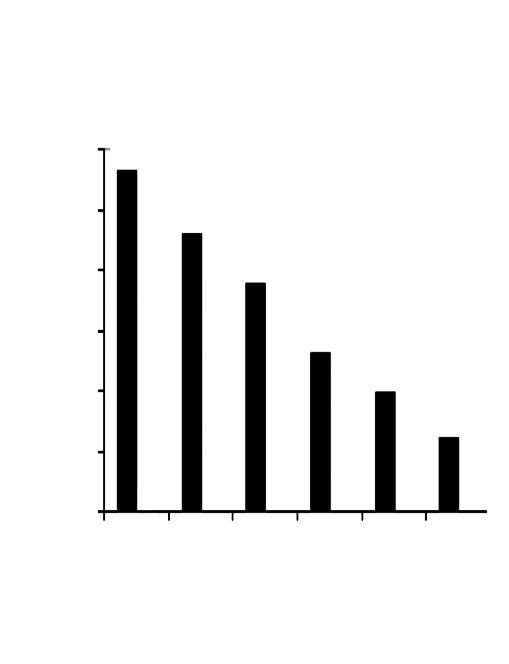

Aumento del numero dei decessi dovuti al cancro nei diversi gruppi di età, dal 1970 al 2000

Età dei pazienti 70 - 79 anni

Età dei pazienti 60 - 69 anni

Età dei pazienti 50 - 59 anni

Dati statistici per gli USA, dati comparabili per l’Europa. Fonte: Journal of the American Medical Association, 2005